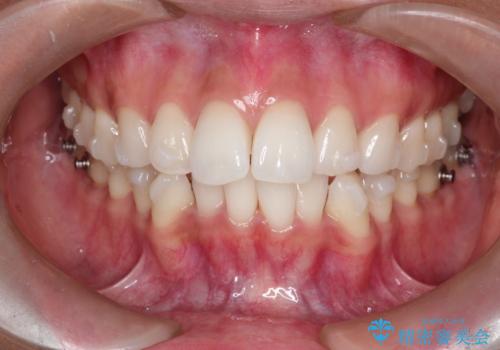

前歯のがたつきをマウスピース矯正で改善。IPRと遠心移動による非抜歯インビザライン治療

精密検査の結果、歯を並べるためのスペースが不足していましたが、抜歯をせずに改善したいというご希望があったため、IPR(歯の側面をわずかに削る処置)と、奥歯を後ろに動かす「遠心移動」を組み合わせる計画を立案。透明なマウスピース装置であるインビザラインを使用し、無理のない範囲でスペースを確保しながら歯列を整えることとしました。

治療では、マウスピースの設計に基づき、奥歯から順に後ろへ移動させる遠心移動を行い、前歯のためのスペースを作りました。同時に、数箇所の歯の間にIPRを施すことで、歯の健康に影響のない範囲で精密に隙間を確保しました。

1年半の治療期間を経て、重なり合っていた前歯はスムーズに整列し、理想的なアーチ状の歯並びへと改善されました。抜歯を行わずに治療を完了したことで、噛み合わせのバランスを維持しながら、審美性を大きく向上させることができました。現在は保定期間に入り、美しい状態を維持されています。